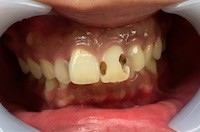

●詰め物や被せ物の段差

詰め物や被せ物を作るとき、詰め物や被せ物の種類によって削り方を変えるなどして、歯と段差ができるだけ生じないように気をつけて作ります。

しかし、どれだけ精密に作ったとしても、わずかな段差が生じるのは避けられません。

虫歯の原因である虫歯菌の潜むプラークは、こうした段差を好むので、詰め物や被せ物の段差はプラークの温床となりやすく、虫歯の再発する原因となってしまいます。

●コンポジットレジンの劣化

小さな虫歯の治療では、現在、コンポジットレジンというプラスチック材料がよく使われています。

コンポジットレジンは、ベースレジンとフィラーという粉末成分を組み合わせて作られているのですが、時間が経つとフィラーが少しずつ取れていき、表面に目に見えないような穴が開きます。

この部分もプラークがつきやすく、やはり虫歯が再発しやすくなります。